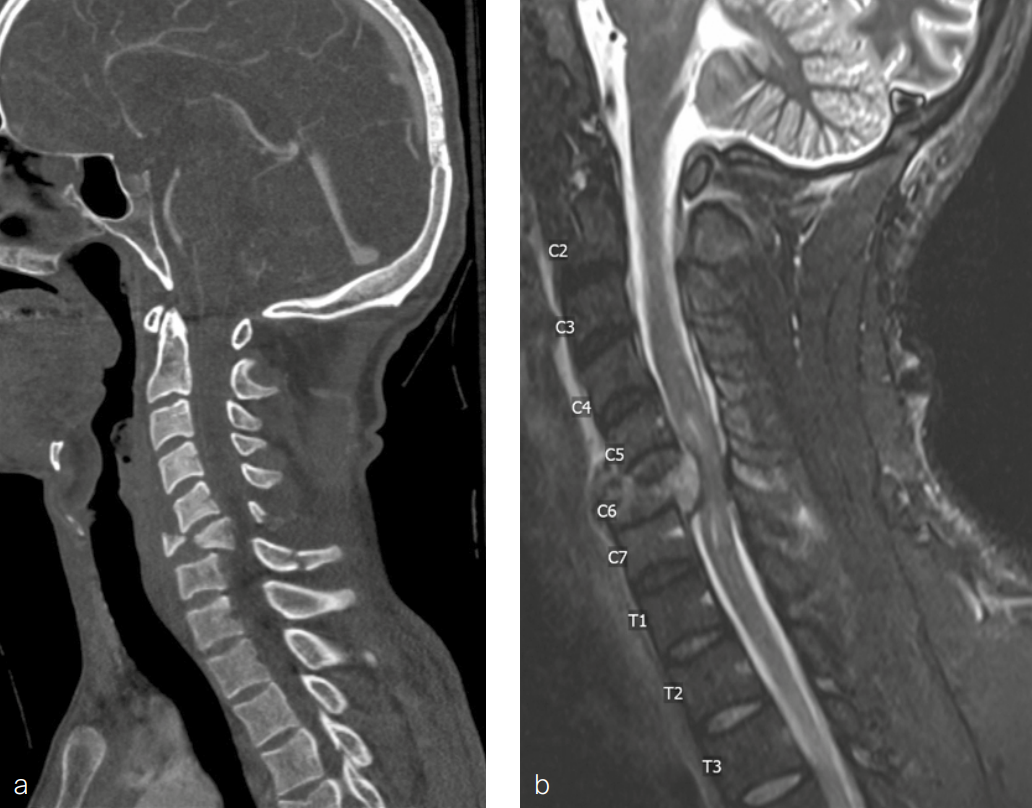

A 34-year-old man with a history of alcohol use disorder and prior seizures was admitted to hospital after being found outside his house having reportedly fallen from a second-story window. The patient had numbness and left-sided deficits, did not recall the circumstances of the fall, and was very intoxicated in the emergency department.

Full-spine imaging (Fig 10) showed injuries including a C6 flexion distraction with significant burst fracture (AO C6 B2 A4) with retropulsion into the canal and associated kyphosis, with an associated mildly displaced C6 spinous process fracture, C7 displaced spinous process fracture, occipital condyle fractures without extension into the facets, and transverse process fractures of T11, L1, L2, L3, and L4.

Other injuries included fractures of ribs 10–12 on the left side, left pneumothorax and lung contusion, left vertebral artery occlusion, and hemorrhagic contusions of frontal lobes and temporal lobes.

Physical examination showed muscle weakness in the left upper extremity, especially in the hand, and reduced sensation in the left upper extremity (C5–T1). The lower extremities had normal muscle strength and sensation.

The patient underwent a C6 corpectomy with removal of fractured C6 vertebral body, restoration of height and placement of a Synmesh cage filled with autograft from the fracture. Following restoration of height and vertebral body reconstruction, a CODA™ ACP plate was applied anteriorly with screws into the C5 and C7 vertebral bodies. Given the psychosocial nature of the patient and the fracture pattern, the patient was then placed prone and underwent posterior instrumentation with Symphony instrumentation with lateral mass screws into C5 and C6 bilaterally and pedicle screws into C7 followed by placement of 4 mm rods along with fusion (Fig 11). The patient did well postsurgery (Fig 12) and was discharged according to protocol, but was unfortunately then lost to follow-up.